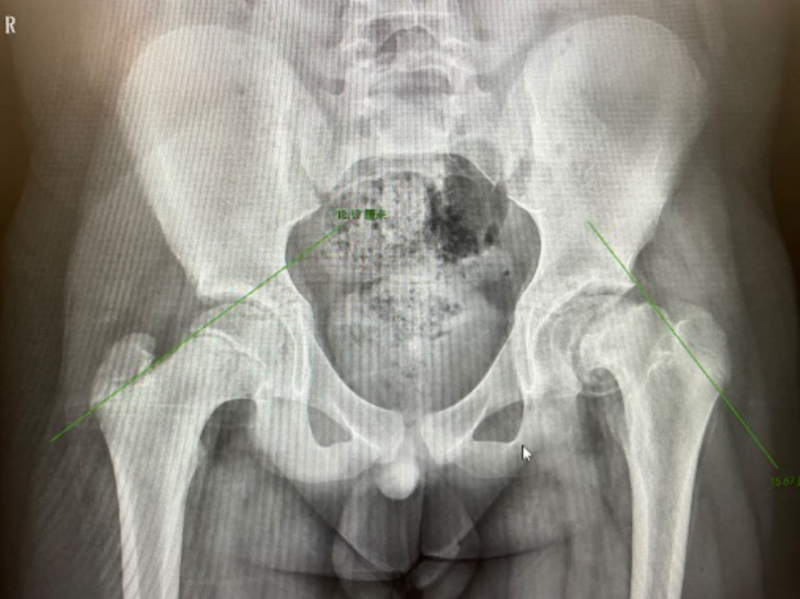

術(shù)前X片影像

經(jīng)過檢查,小明被診斷為“慢性左股骨頭骨骺滑脫(重度)”。因為小明受傷已有一年之久,滑脫的骨骺已經(jīng)畸形愈合,因此手術(shù)不僅要“打斷骨頭”,復(fù)位固定的同時還要盡可能保護患者的股骨頭,盡量避免股骨頭壞死的發(fā)生。經(jīng)過周密的術(shù)前準備,創(chuàng)傷骨科團隊制定了詳細的手術(shù)方案,采用改良Dunn手術(shù)技術(shù)解剖復(fù)位滑脫骨骺,最終順利完成手術(shù)。